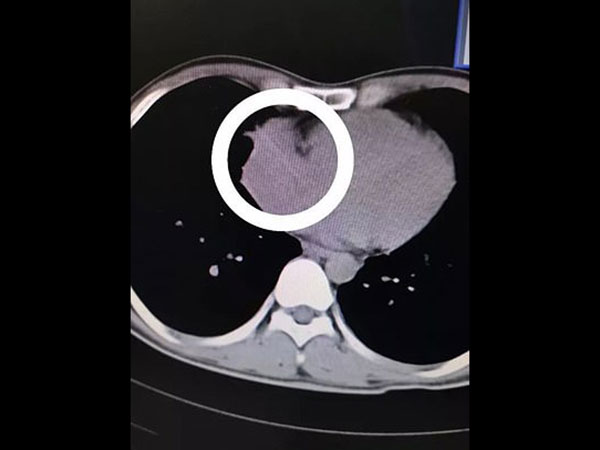

ಸುಮಾರು ಆರು ಸೆ.ಮೀ.ಉದ್ದವಿದ್ದ ಟೂಥ್ ಪಿಕ್ ಝೊಯು ಹೃತ್ಕರ್ಣದಲ್ಲಿ ಸಿಲುಕಿಕೊಂಡಿತ್ತು ಎಂದು ವೈದ್ಯರು ತಿಳಿಸಿದ್ದಾರೆ. ಟೂಥ್ ಪಿಕ್ ಶ್ವಾಸನಾಳದ ಮೂಲಕವಾಗಿ ನೇರವಾಗಿ ಹೋಗಿ ಆ ವ್ಯಕ್ತಿಯ ಬಲಭಾಗದ ಶ್ವಾಸಕೋಶದ ಮೂಲಕ ಹಾದು ಹೋಗಿ ಹೃದಯದಲ್ಲಿ ಸಿಲುಕಿಕೊಂಡಿದೆ ಎನ್ನುವುದು ವೈದ್ಯರ ಹೇಳಿಕೆ.